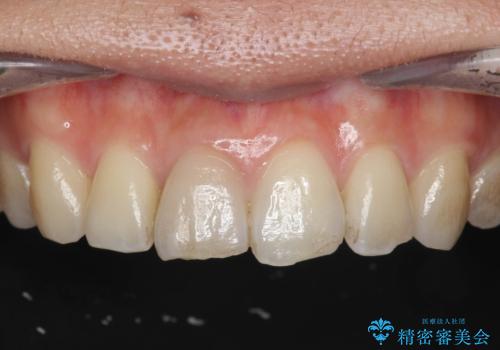

前歯の変色 打撲により失活した前歯の根管・セラミック治療

- 変色してきた前歯の形態回復、色調の改善を求めて来院されました。

自然な色調をセラミッククラウンで再現することができ、審美性の改善に大変喜んでいただくことができました。